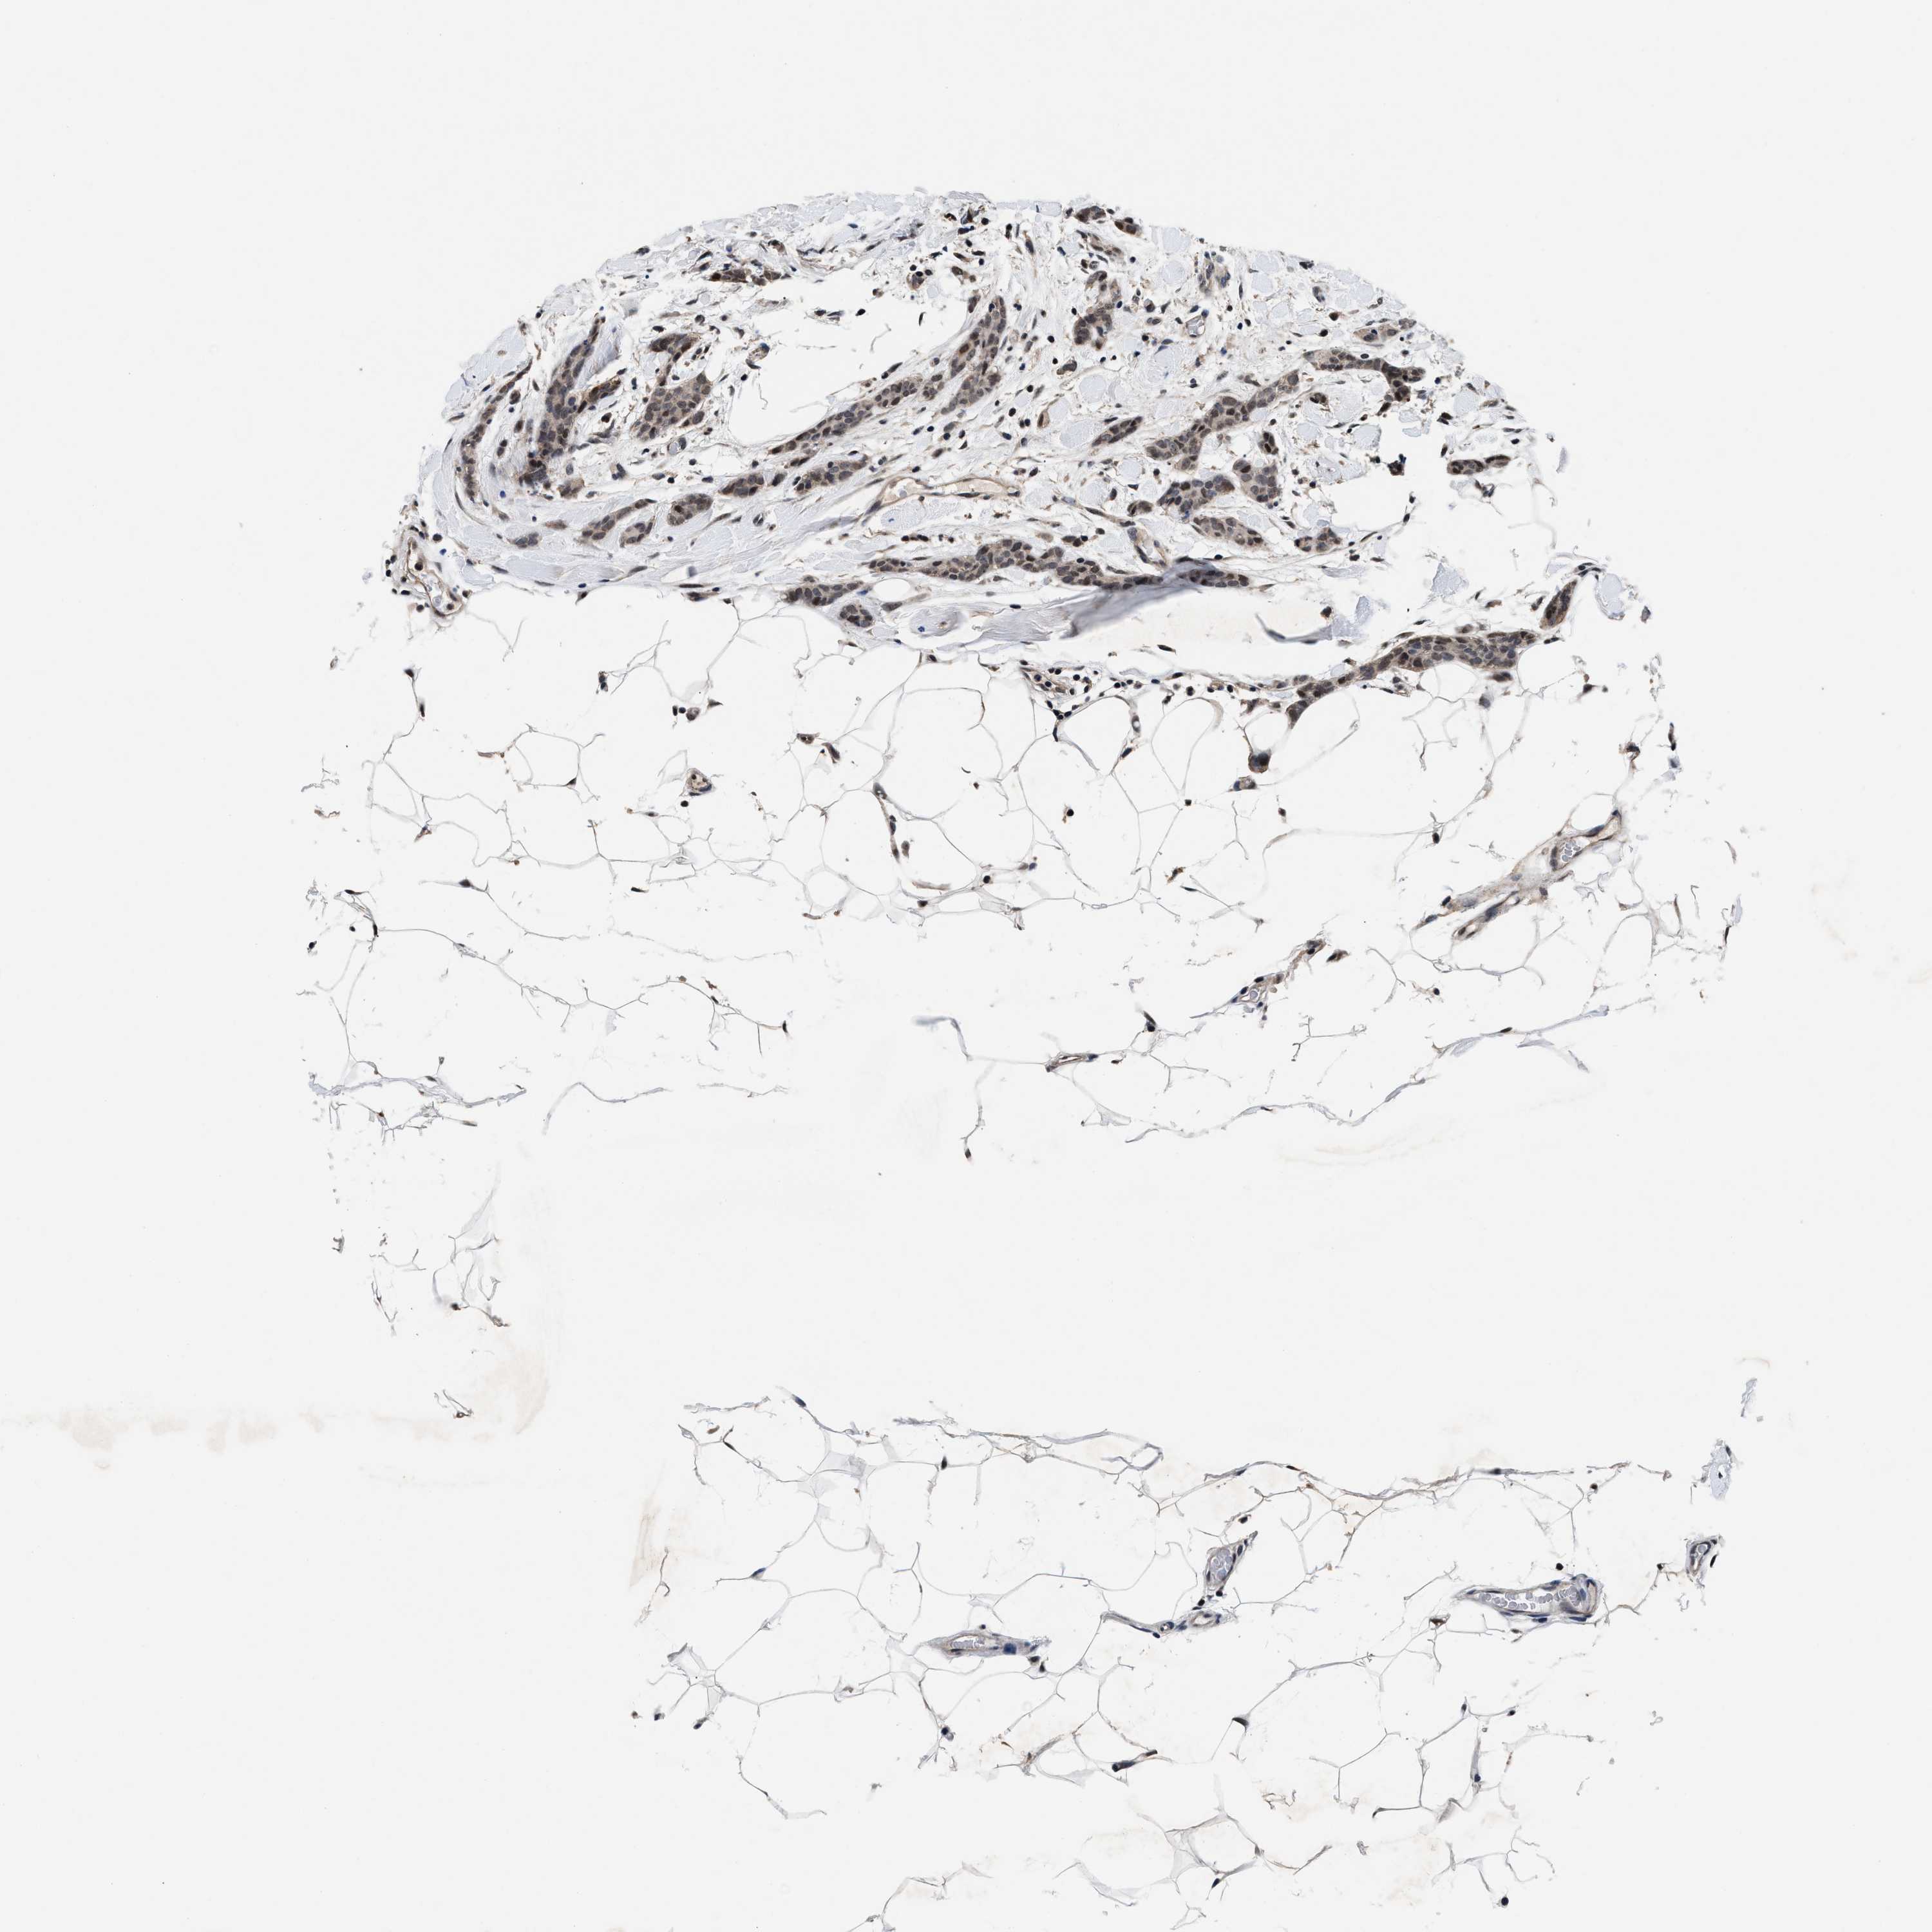

BRCA TCGA BRCA VALIDATION PROTEIN EXPRESSION

ANTIBODIES

AND

VALIDATION